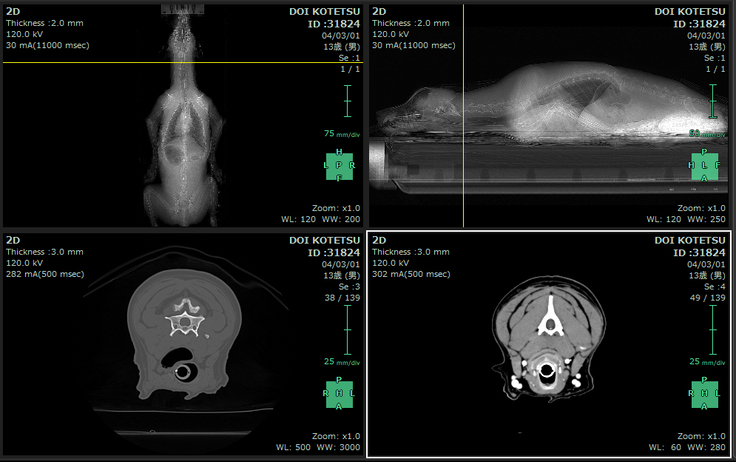

▽こてつのCT画像です(2022/3/1)

「喉頭麻痺」を改善するための手術として

被裂軟骨側方化術(タイバック)、永久気管切開術を予定しておりますが、

手術内容、治療方法が変わる可能性もあります。